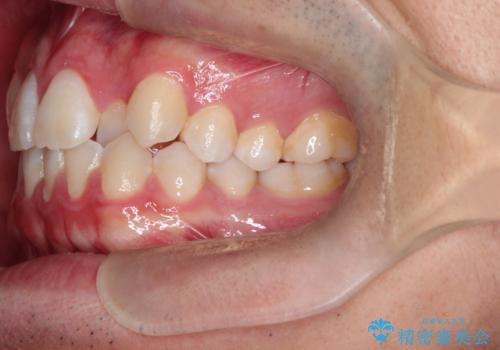

正中の改善と前歯の整列:抜歯を伴う矯正治療の症例

- 前歯のガタガタや正中の不整を改善するために、右上4、左上4、左下4を抜歯し、矯正治療を行いました。この治療により、見た目だけでなく、咬合のバランスも改善され、患者様の口腔内の健康が向上しました。